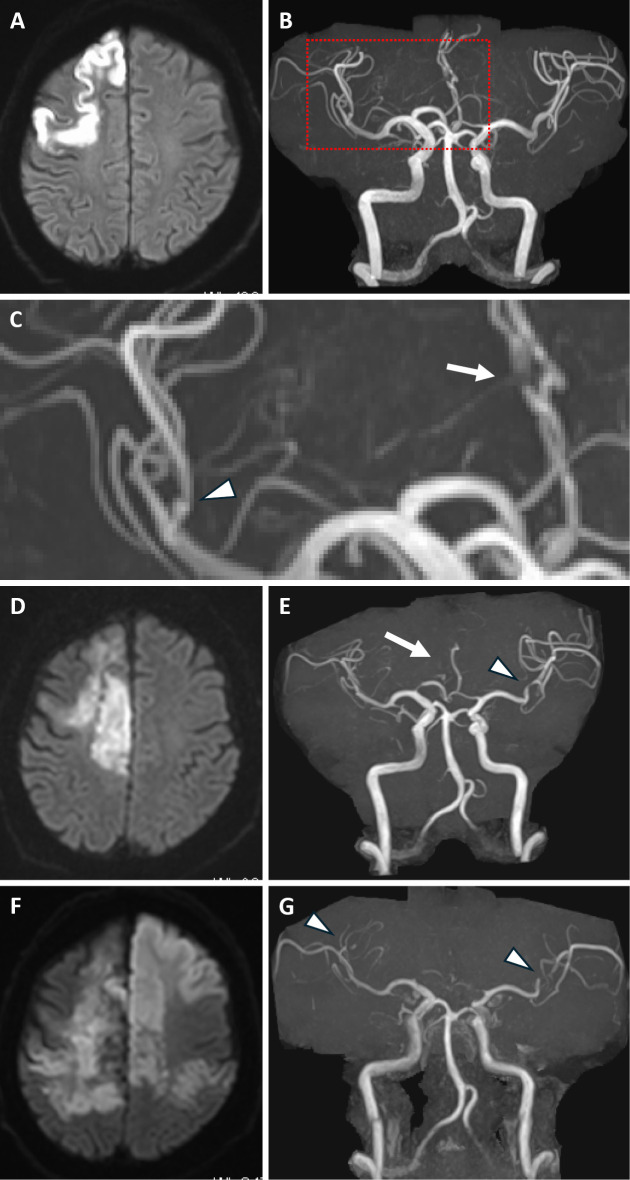

We herein report an autopsy case of multiple cerebral infarctions caused by varicella-zoster virus (VZV) vasculopathy. A 60-year-old man, previously diagnosed with VZV uveitis, subsequently developed cerebral infarction with multiple cerebral vessel stenoses. Based on the results of a polymerase chain reaction test of cerebrospinal fluid, the patient was diagnosed with VZV vasculopathy. Despite treatment with acyclovir and prednisolone, the vascular stenosis progressed and became complicated by extensive cerebral infarctions. Upon autopsy, inflammatory cell infiltration was pathologically observed in the vessel walls of the anterior and middle cerebral arteries, consistent with the magnetic resonance imaging findings.